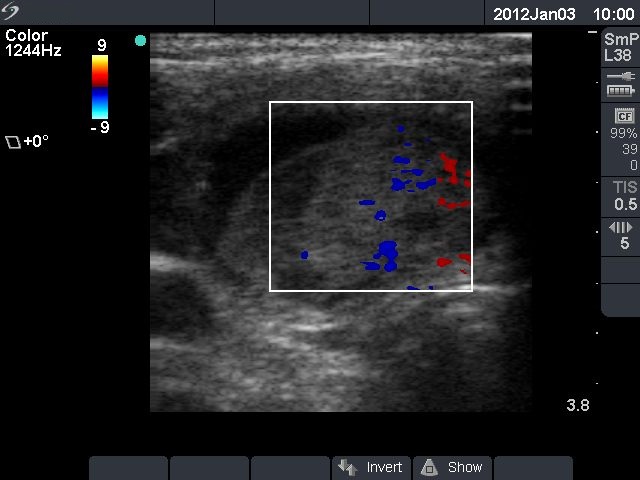

Ethanol sclerotherapy: thyroid cysts - Case 1

Initial investigation (ultrasonographic picture 3)

Isthmic part of the right lobe, horizontal scan, color Doppler mode. The vascularization is not specific.